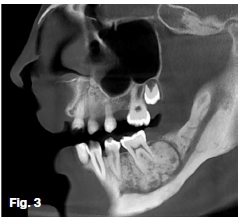

CBCT imaging and analysis was performed. Observe unilateral expansion by the distending soft tissue outline illustrated through 3D rendering (Figure 2). Sagittal oblique (Figure 3) and axial (Figure 4) slices depict a round heter-ogenous predominantly high-density lesion with an encompassing thin uniform less dense peripheral band. Irregular root resorption, displacement of the inferior alveolar nerve canal, buccal-lingual cortical expansion, thinning, and interruption was apparent. Irregular thickening at the inferior border and surrounding osteosclerosis were noted. A macroscopic view (Figure 5), photomicrograph (Figure 6), and conventional radiograph (Figure 7) of vertically sectioned surgical specimens of similar lesions. Note the intimate relationship with the tooth roots.